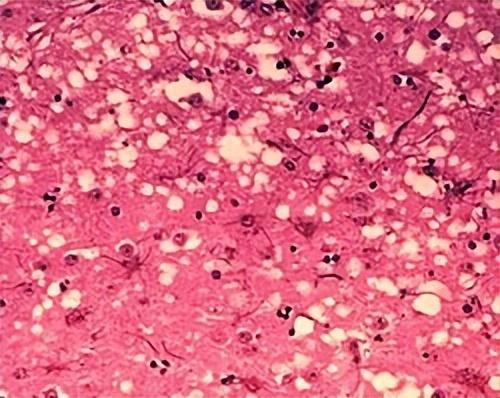

感染牛海綿狀腦病(BSE)的牛隻產生腦組織空洞化現象,或稱神經退化

(圖片來源:wikipedia)